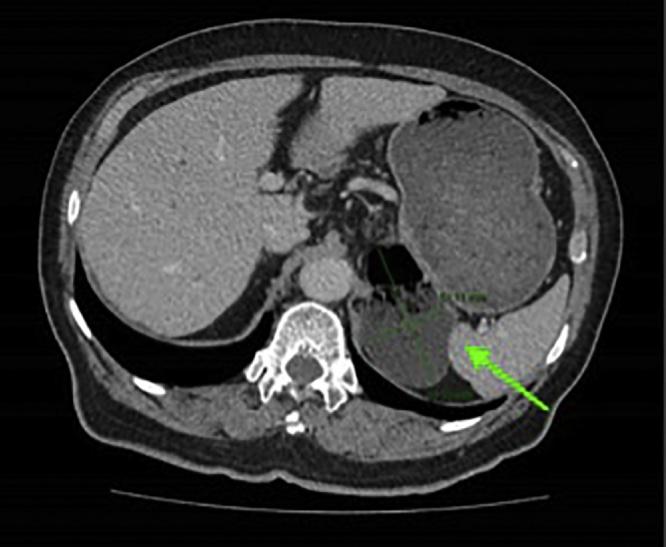

CASE PRESENTATION

A 77-year-old gentleman presented to the outpatient clinic with a one-month history of passing black stools. He was arranged for an oesophagogastroduodenoscopy (OGD) which revealed a gastric body polyp and a diverticulum in the fundus of the stomach.

一名77岁男性到门诊就诊,有一个月排黑便病史。他接受了食管胃十二指肠镜检查(OGD),结果显示胃体部有息肉,胃底部有一个憩室。